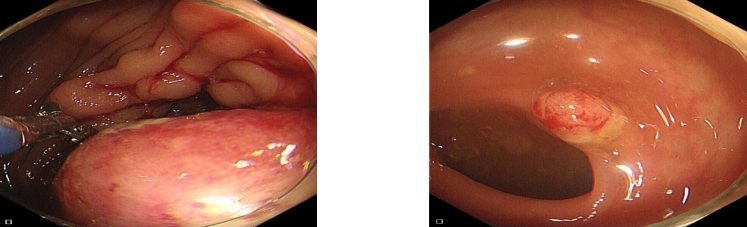

图2 肠镜可见升结肠一隆起肿物及乙状结肠息肉Fig.2 Colonoscopy revealing a protruding mass in the ascending colon and a sigmoid colon polyp